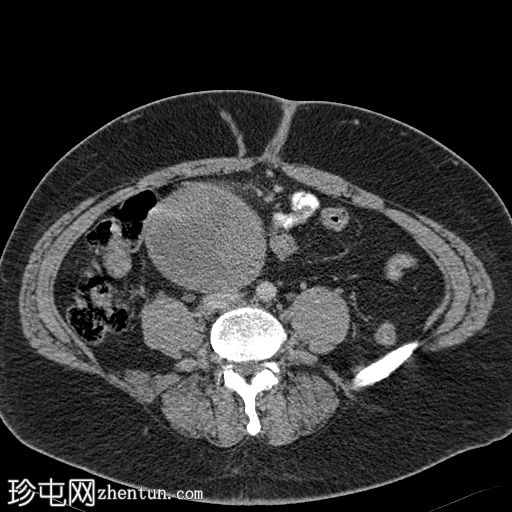

轴位增强扫描(门静脉期)

盆腔内可见一大小为12 x 17 cm的边界清晰的异质性软组织肿块,向下延伸至下腹部。肿块内未见钙化或脂肪密度影。肿块向下推挤膀胱,并牵拉周围肠袢,但无放射学侵犯证据。未见明显淋巴结肿大、腹水或气腹。未见肺部或骨骼局灶性病变。肝脏可见数个小的单纯性囊肿。患者存在少量Bosniak I型肾囊肿,双侧肾盂肾盏系统饱满。曾行胆囊切除术。